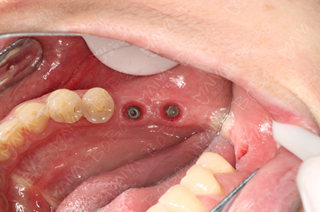

种植牙后口腔内全景片

种植完成后的牙齿情况